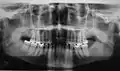

Es imprescindible que todo profesional tenga conocimientos para realizar este tipo de proyecciones de forma aceptable y esté capacitado para su lectura e interpretación. Son, por tanto, en su ejecución e interpretación, del total dominio del odontólogo o del estomatólogo. Únicamente el empleo de una técnica radiográfica llevada a cabo con precisión aporta radiografías intrabucales interpretables. Las técnicas intrabucales se utilizan preferentemente para diagnósticos dentarios y peridentarios, aunque muchas veces son una ayuda muy valiosa para matizar ciertos detalles en estudios más amplios del macizo maxilofacial. Destaca la utilización en cirugía bucal de las técnicas de desplazamiento, horizontales o verticales, para la localización anatómica de dientes retenidos o cuerpos extraños, y la obtención de imágenes con gran definición de zonas concretas que facilitan la realización de un diagnóstico. También se usa la radiografía intrabucal en la valoración de la osteointegración de los implantes intraóseos.

Su nombre, radiografía intrabucal, se debe, naturalmente, a que las películas se colocan dentro de la cavidad bucal. Según el tamaño y la colocación de las películas, se pueden clasificar en procedimientos periapicales o retroalveolares, interproximales o de aleta mordida y oclusales. Un requisito imprescindible previo para la realización de la radiografía intrabucal es retirar prótesis metálicas removibles, dispositivos ortodóncicos o cualquier objeto metálico que se encuentre en el área a estudiar. Además, es necesaria la inmovilización perfecta de la cabeza del paciente en la posición idónea.

- Las técnicas periapicales o dentoalveolares, sirven para explorar el diente en su totalidad, desde la corona hasta el ápice, el espacio periodontal y el tejido óseo que lo rodea. Se puede realizar mediante dos procedimientos: la técnica de bisectriz y la de planos paralelos.

- Las técnicas interproximales o de aleta mordida son muy útiles para el estudio sistemático y la exploración de la caries dental. Se aprecian caries interproximales y oclusales, pero también alteraciones pulpares, restauraciones desbordantes, recidivas de caries bajo éstas, ajustes de prótesis fijas, cresta alveolar, límite amelocementario…en una misma película se observan las regiones coronal y cervical de los dientes superiores e inferiores a la vez. El examen es cómodo y rápido, ya que las películas no se clavan en el suelo bucal; por este motivo es una exploración habitual para la detección de caries interproximales en niños.

- Las técnicas oclusales se denominan así porque la colocación y sujeción de la película se realizan en el plano oclusal, entre el maxilar y la mandíbula, dirigiéndose el haz de rayos desde arriba o desde abajo, perpendicular u oblicuamente. Se utilizan como complemento de los procedimientos periapicales, para estudios más amplios de áreas óseas, fracturas alveolares, palatinas o del cuerpo mandibular, límites de lesiones quísticas o tumorales, dientes incluidos y cuerpos extraños.